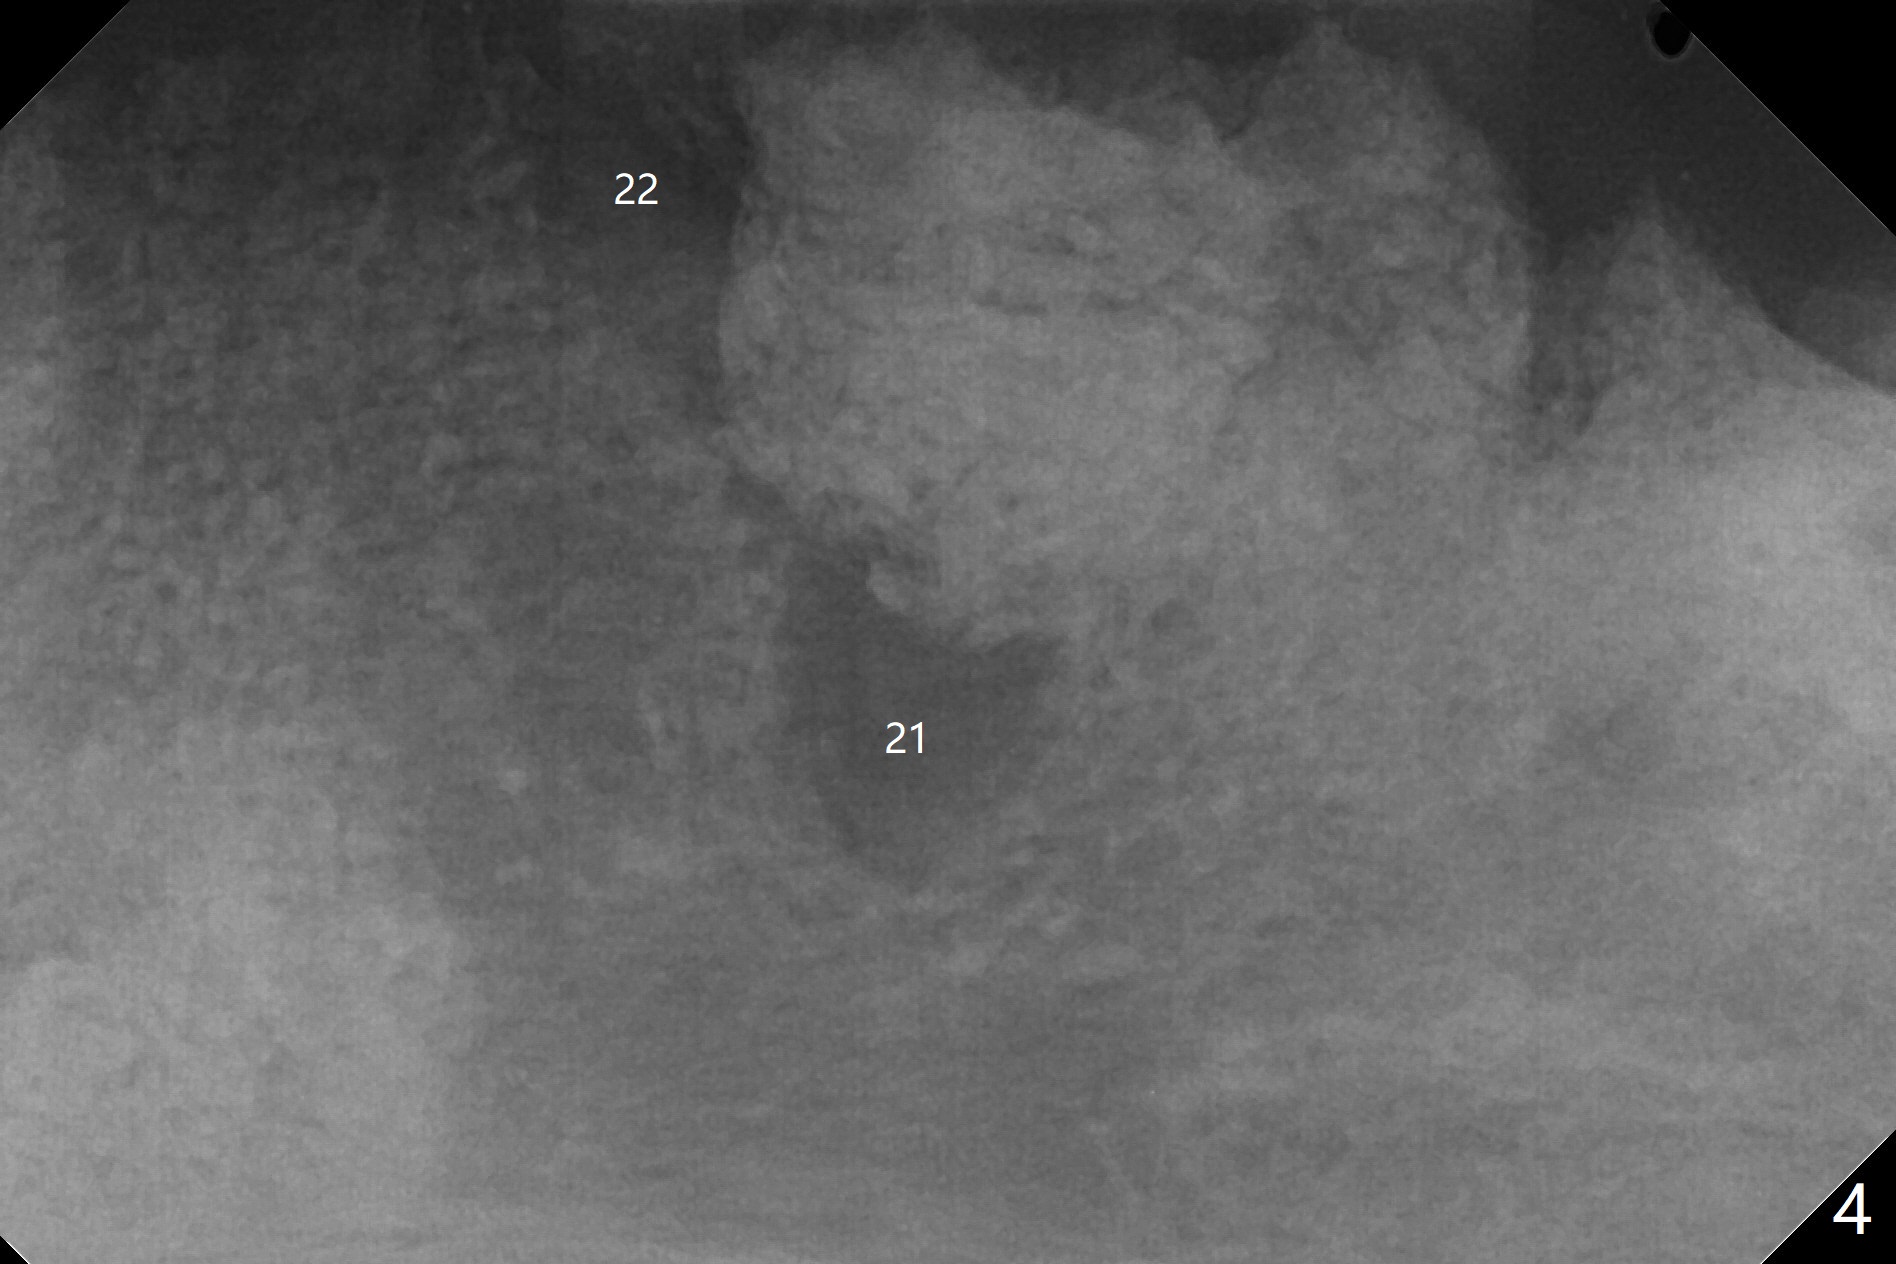

A 84-year-old man (uncontrolled diabetes) requests extraction of terminal teeth (#17, 20-22) for complete denture (Fig.1-3). He does not have finance for implants now. After extraction and debridement, 1 cc of Bond Apatite is applied to the sockets (Fig.4-6). The sockets at #20-22 are primarily closed with 4-0 PGA (Fig.7), while that of #17 with 4-0 Chromic gut suture over Osteogen Plug (a type of Collagen Plug, Fig.8). PGA sutures remain in place (Fig.9,10), while Chromic Gut ones dissolve 7 days postop (Fig.11). The ridge at the extraction sites remains robust 2 months postop (Fig.12). The sockets seem to remain radiopaque 2 months postop (Fig.13).